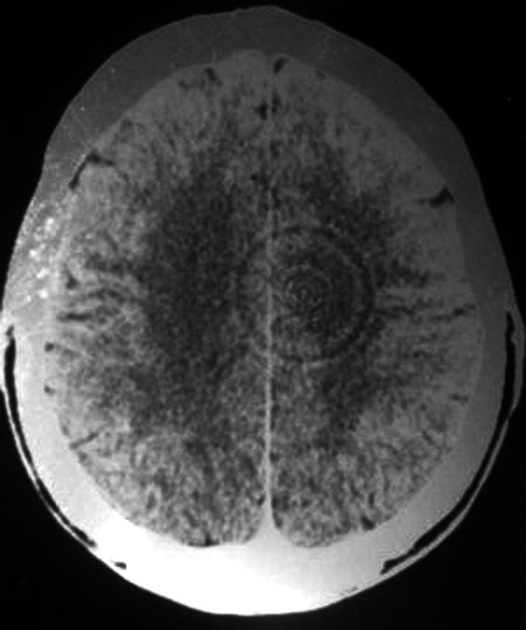

Ring artifact

due to miscalibration or failure of one or more detector elements in a CT scanner. can also be caused by insufficient radiation dose, contrast material contamination of the detector cover

occur close to the isocenter of the scan and are usually visible on multiple slices at the same location. common problem in cranial CT.

remedy is usually simple, recalibrate the scanner, or replace detector element